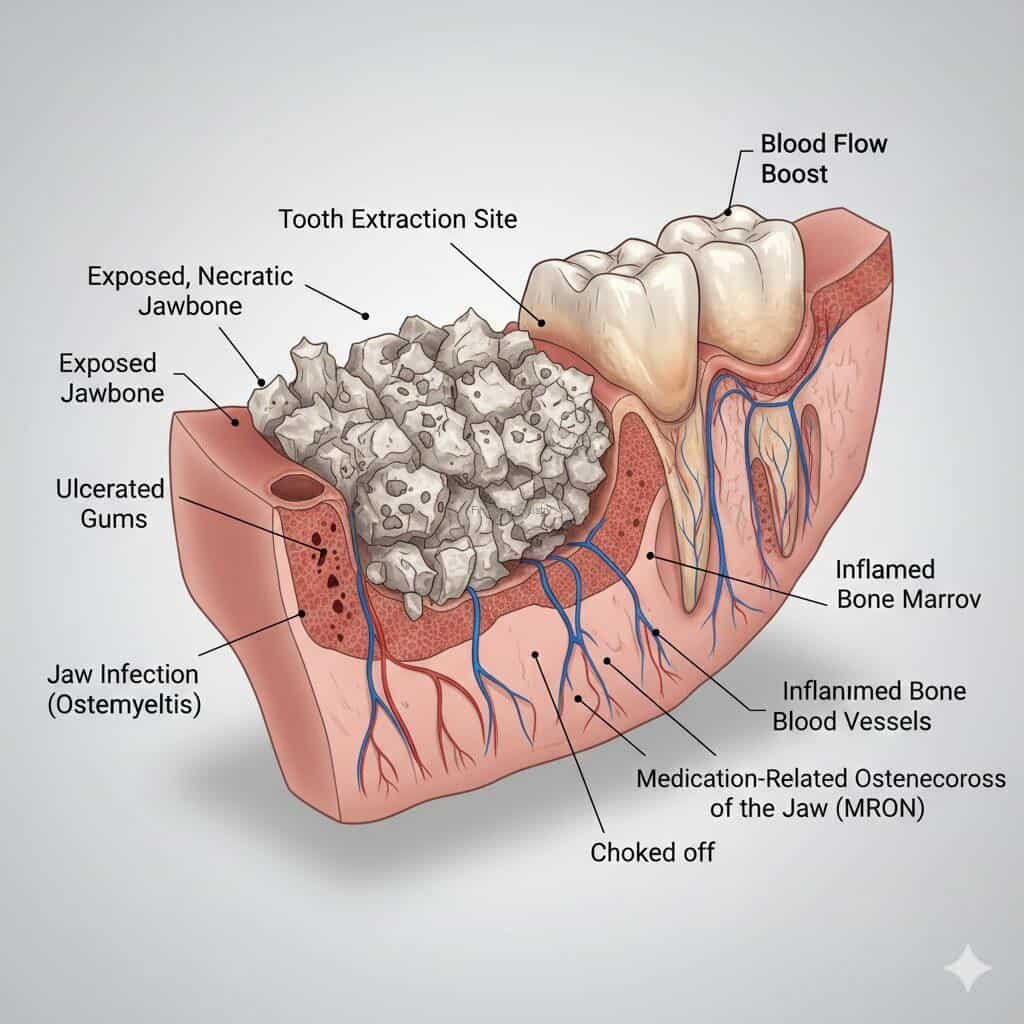

1. What exactly is MRONJ?

(Medication-related osteonecrosis of the jaw: definition and best practice for prevention, diagnosis, and treatmentNicolatou-Galitis, Ourania et al.Oral Surgery, Oral Medicine, Oral Pathology and Oral Radiology, Volume 127, Issue 2, 117 – 135)

MRONJ stands for Medication-Related Osteonecrosis of the Jaw. It is a condition where an area of the jawbone fails to heal and remains “exposed” (you can see or feel the bone through your gums) for more than 8 weeks.

- The Evolution: Originally known as BRONJ (limited to Bisphosphonates), the American Association of Oral and Maxillofacial Surgeons (AAOMS) expanded the term to MRONJ in 2014 to include other agents like denosumab and anti-angiogenics that also affect the jaw.